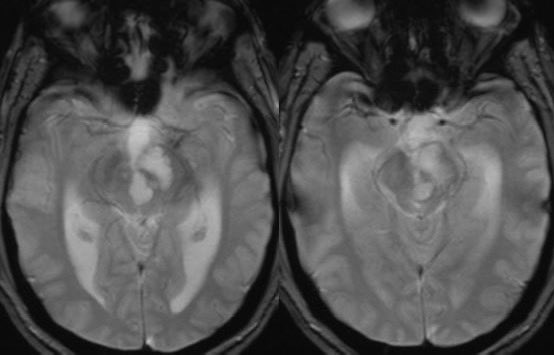

What is the most likely diagnosis in this 30 y/o M presenting with headaches? 🧠

🔷More images in 🧵